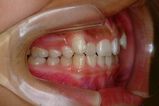

矯正前                 矯正後

治療前 の 左 です 動く矢印治療後 の 左 です

治療前 の 右 です 動く矢印治療後 の 右 です